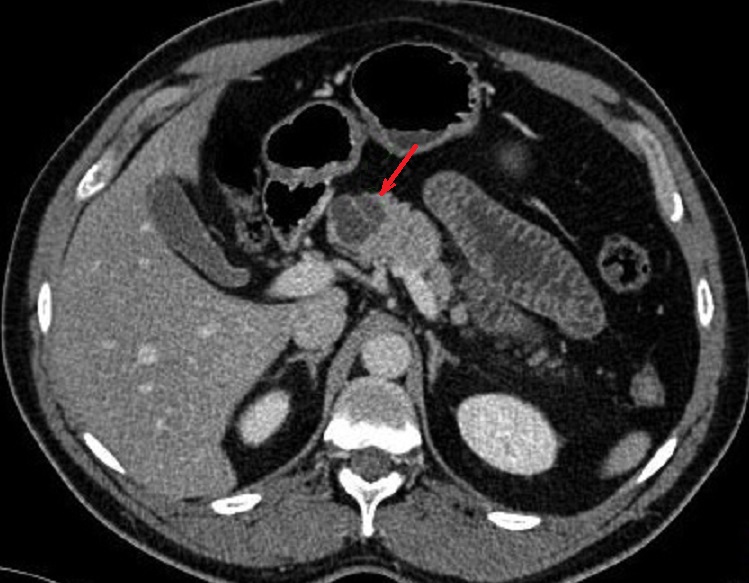

Image radiologique TDM d'une

cystadenome sereux multikystique cephalique du

pancreas a aspect multikystique comporte de plusieur

kyste hypodensite de < 2cm situe a la tete du

pancreas ( fleche rouge ) . Coupe TDM axcilaire |